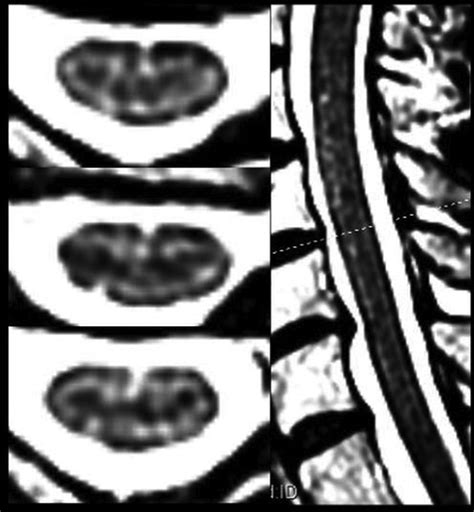

The anterior fissure spinal cord is a longitudinal groove that runs along the anterior (front) surface of the spinal cord. This fissure is a prominent anatomical landmark that helps in identifying the anterior median sulcus, which is a shallow groove that runs along the midline of the anterior surface of the spinal cord. The anterior fissure is continuous with the anterior median fissure of the medulla oblongata, which is part of the brainstem.

The anterior fissure is significant because it marks the boundary between the left and right halves of the spinal cord. It is also the site where the anterior spinal artery runs, providing blood supply to the anterior two-thirds of the spinal cord. This artery is crucial for the functioning of the motor neurons and the sensory pathways that transmit pain and temperature sensations.

• Diagnostic Imaging: Magnetic resonance imaging (MRI) and computed tomography (CT) scans can be used to visualize the anterior fissure and assess its integrity. These imaging techniques are essential for diagnosing spinal cord injuries and neurological disorders.

• Imaging Techniques: MRI and CT scans are essential for visualizing the spinal cord and the anterior fissure. These imaging techniques can help identify structural abnormalities, such as tumors or fractures, and assess the integrity of the anterior spinal artery.